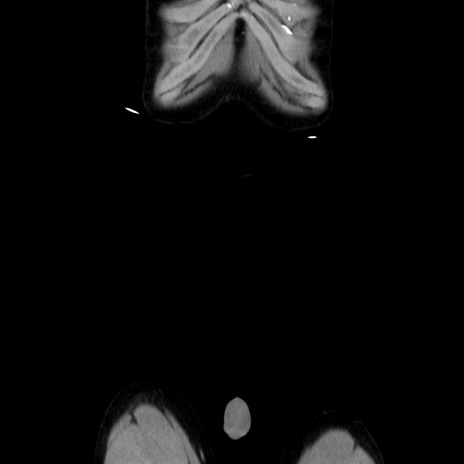

横断像